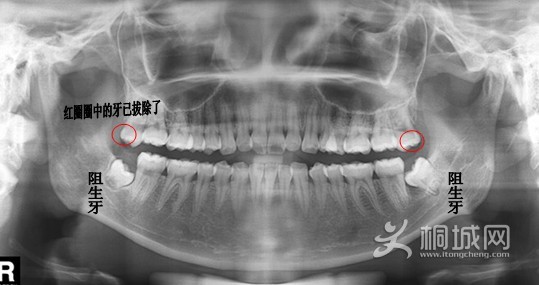

智齿长什么样子,看以上这张图就一目了然啦~

智齿(Wisdom Tooth)是指人类口腔内,牙槽骨上最里面的上下左右各一的四颗第三磨牙。因为这四颗第三磨牙正好在20岁左右时开始萌出,此时人的生理、心理发育接近成熟,于是被看做是“智慧到来”的象征,故称它为“智齿”——智慧之齿。

71cf3bc79f3df8dc6cdebf06cd11728b46102841.jpg

下面开始拔智齿了哦,看完记得要淡定哈~